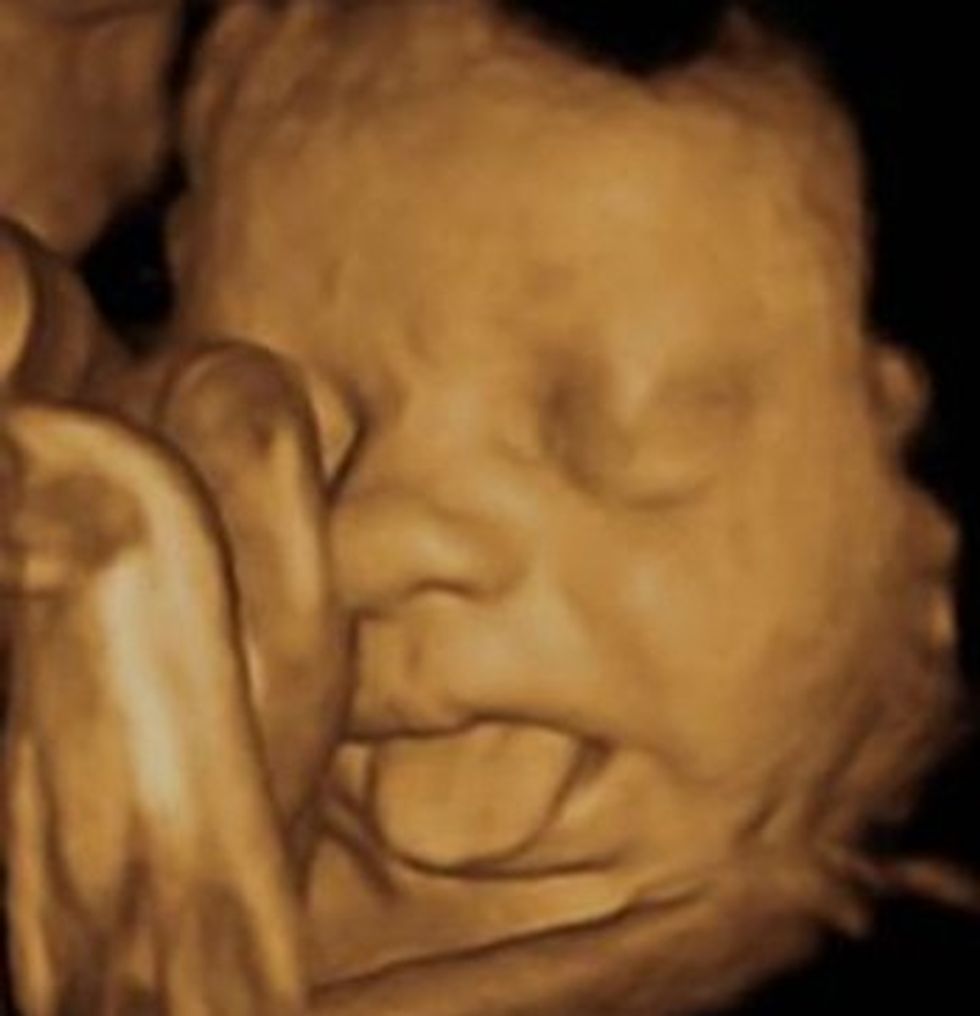

Edhe diagnostika me ultratingull është zhvilluar në fushën e rekonstruimeve në shumë rrafshe, dhe fëmija akoma gjatë shtatzënisë me ultratingull mund të shikohet me 3D dhe 4D për tu analizuar gjendja e tij shëndetësore.